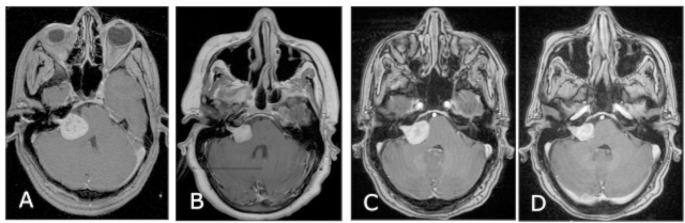

Late: tumor enlargement occurred after 3 years of treatment (Fig. 1). It was found in 30 patients (21%) starting at a mean of 59 months (37–162 months).

Twenty-seven patients underwent salvage treatment. Nineteen patients (71%) underwent GK re-treatment alone, six patients (22%) underwent surgery alone, and two patients (7%) had surgery then GK re-treatment. The median follow-up duration after salvage treatment was 68 months (4–160 months). The tumor volume according to salvage treatment was; mean 5.4 cc (0.5–15.8 cc) for GK re-treatment alone (Fig. 4), mean 14.9 cc (5–30 cc) for surgery alone, and mean 12.6 cc (12–13.2 cc) for surgery followed by GK re-treatment. The five patients who underwent surgery alone were lost to follow-up. Tumor control was achieved in 19/21 patients (90%). The actuarial tumor control was 94% at 5 years. The tumors shrank in 15 patients (71%), remained stable in 4 patients (19%), and progressed in 2 patients (10%). The two patients with tumor progression are still being followed up.

GK salvage treatment A At the time of treatment; 3.3 cc tumor was treated with 12 Gy to the 50% isodose with 97% cover, B 6 months after treatment 4.8 cc tumor volume (44% TVCp), C 61 months after treatment; 7.2 cc tumor volume (118% TVCf). GK re-treatment was performed to a 7.2 cc tumor that was treated with 12 Gy to the 50% isodose with 97% cover, D 70 months after 2nd GK treatment; 4.6 cc tumor volume (−36% TVC).